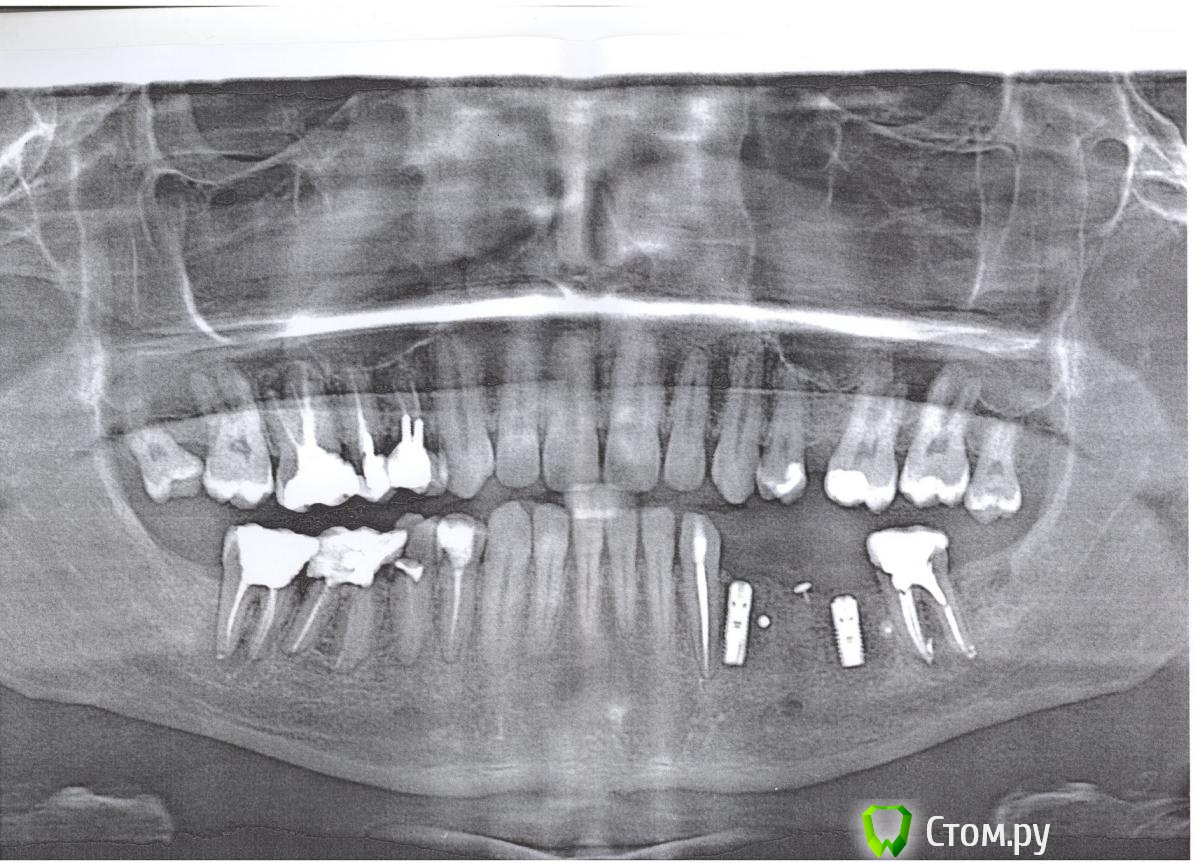

eugen.berend Опубликовано 18 октября, 2014 Поделиться Опубликовано 18 октября, 2014 Приветствую,У меня между 46 и 47 зубами дырка, в которую постоянно попадает еда. Зубочистка заходит в дырку на несколько мм. Нитью хрен вычистишь. 46 и 47 зубы года 4 назад были в процессе терапии очень сильно сточены и на них стояли галимые плоские пломбы на ползуба. В этом году на этих зубах сделали некое "восстановление", которое, как я понимаю, просто восстановило их форму, но не функционал, для чего их надо протезировать коронками.На снимке видно, что в 46 зубе засел сломанный файл. Меня интересует дальнейшая судьба этих, 46 и 47, зубов. Дырка в десне между ними здорово мешает жить. Имеет ли смысл лечить десну, если при попытке вытащить файл из 46 зуба скорее всего будет перфорирован канал и зуб пойдёт под удаление? Какие вообще есть нормальные варианты?Визит к стоматологу только через неделю. Ссылка на комментарий

Korel Опубликовано 19 октября, 2014 Поделиться Опубликовано 19 октября, 2014 (изменено) Хотел бы ошибиться, но Вам вероятно надо удалять не два а три: 45 46 47 И верхние восьмёрки также. Изменено 19 октября, 2014 пользователем Korel Ссылка на комментарий

IvanK Опубликовано 19 октября, 2014 Поделиться Опубликовано 19 октября, 2014 Хотел бы ошибиться, но Вам вероятно надо удалять не два а три: 45 46 47 И верхние восьмёрки также. И очень может быть что это не конец .. 1 Ссылка на комментарий

eugen.berend Опубликовано 21 октября, 2014 Автор Поделиться Опубликовано 21 октября, 2014 можно ли по снимку сказать, насколько срочно требуется удаление 46-47 (и возможно 45)?не возникнут ли проблемы, если его отложить на 5 месяцев? потому что мне только-только вот установили имплантаты на другую сторону нч, и мне попросту нечем будет жевать Ссылка на комментарий

eugen.berend Опубликовано 22 января, 2015 Автор Поделиться Опубликовано 22 января, 2015 Кому интересно, итог таков:45 зуб годен под протезирование46 - удалили инструмент, не повредив канал, в другом канале нашли 1.5 мм обломок, возможно, в следующий раз удастся удалить и его44 47 - не трогали ещёЕщё по поводу кости между 46 и 47 сказали, что если туда не будет забиваться жрат - то она отрастёт. Заложили туда лекарство. Но вот в этом мне почему-то слабо верится Ссылка на комментарий